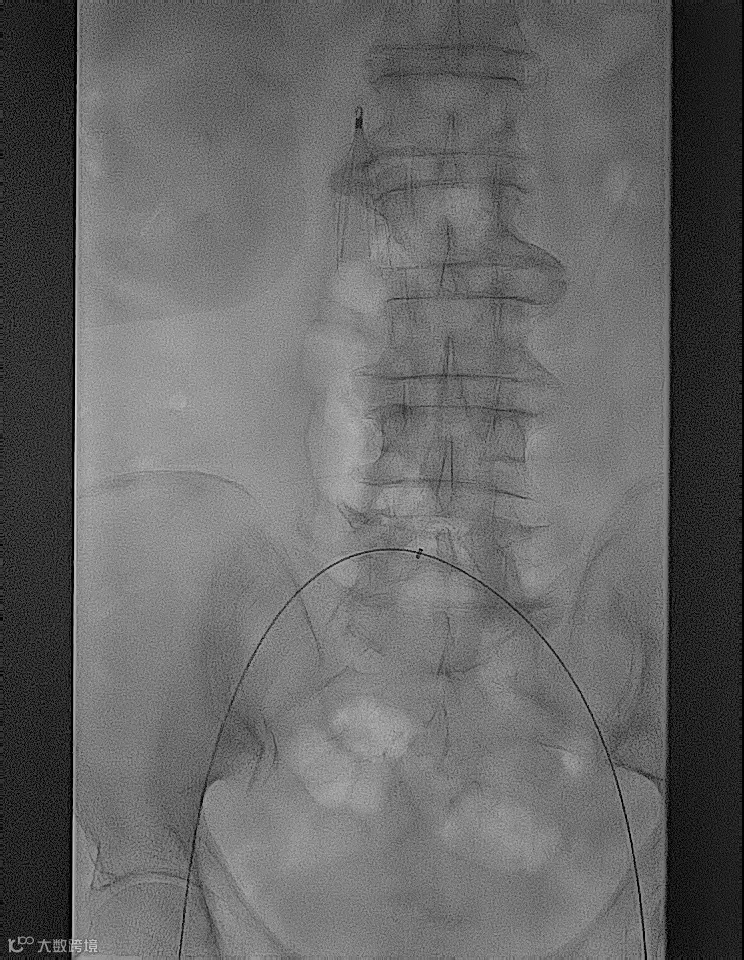

术前造影

手术过程